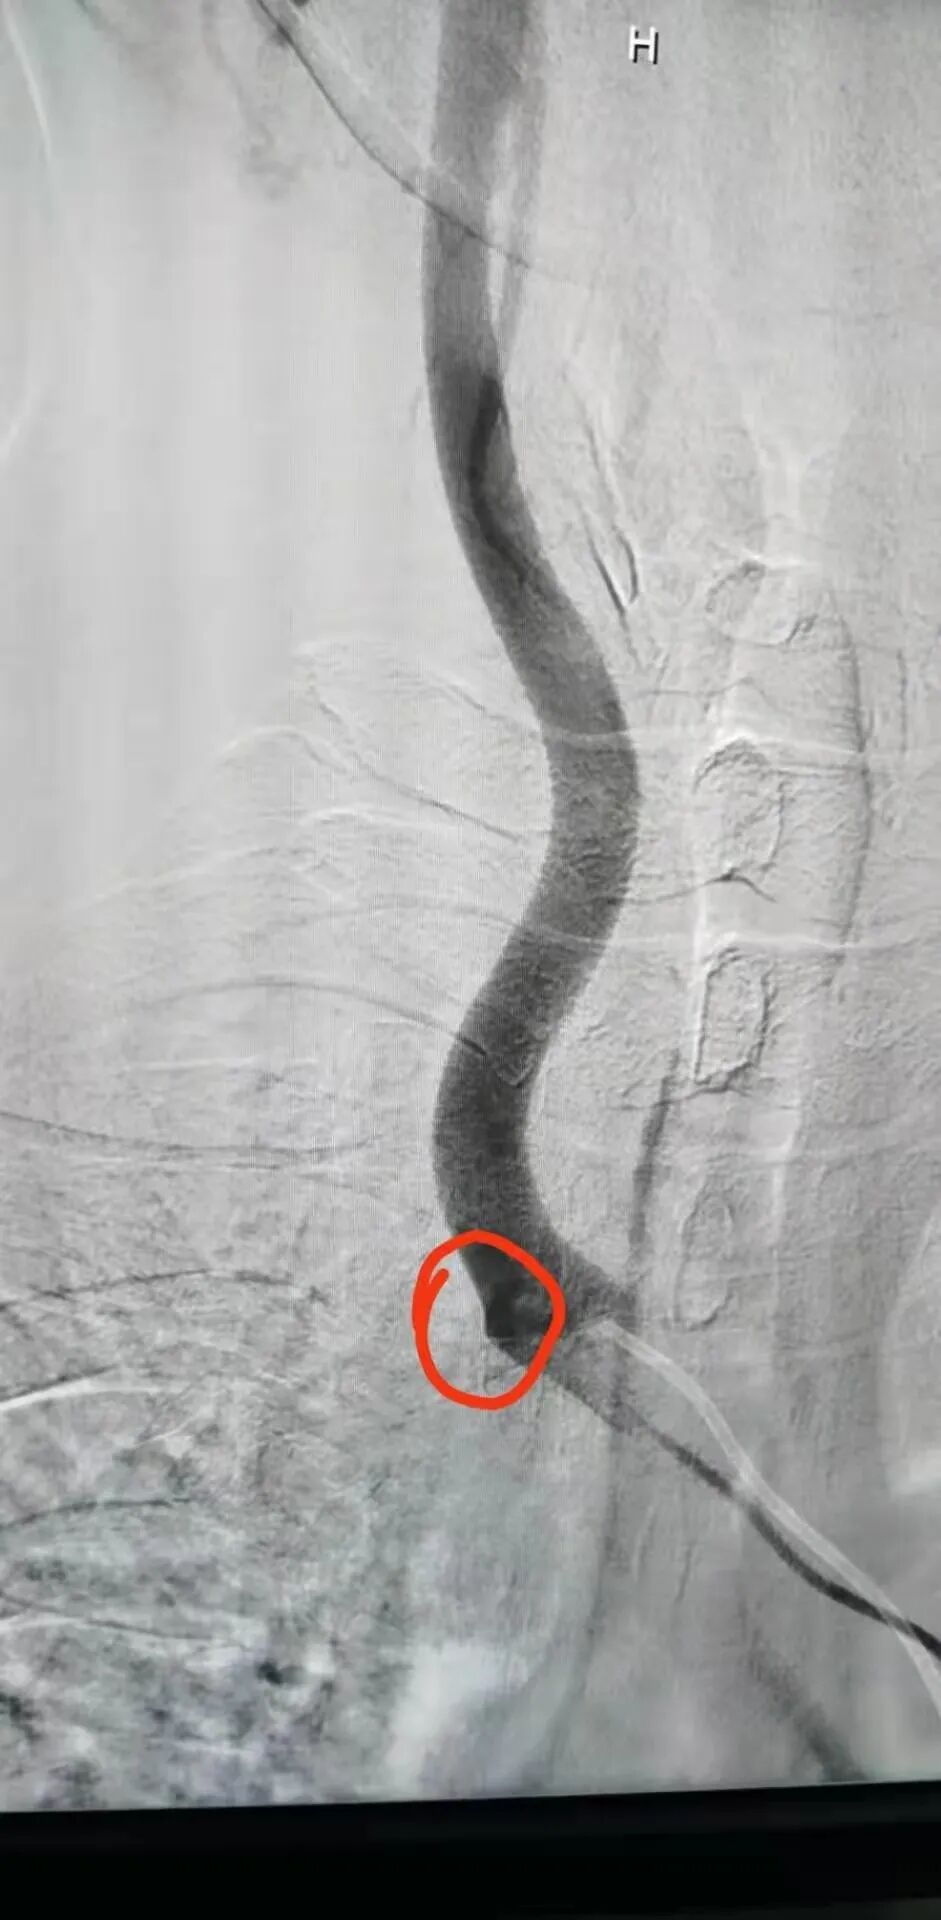

在征得王先生及家人同意后,魏主任组织介入团队进行术前讨论,依据患者病情拟定了详细的手术方案,手术由魏主任亲自操作,在手术中意想不到的遇到了重重困难:一是斑块硬开通困难,二是斑块脱落形成栓塞,三是病灶在夹层,四是支架不能堵塞椎动脉等,给手术带来很大风险,凭借多年的临床实践,终于把血管开通、支架植入。后经造影显示:右锁骨下动脉支架置入后恢复前向血流,不再盗血,手术历时4个小时,整个过程可谓“惊心动魄”。